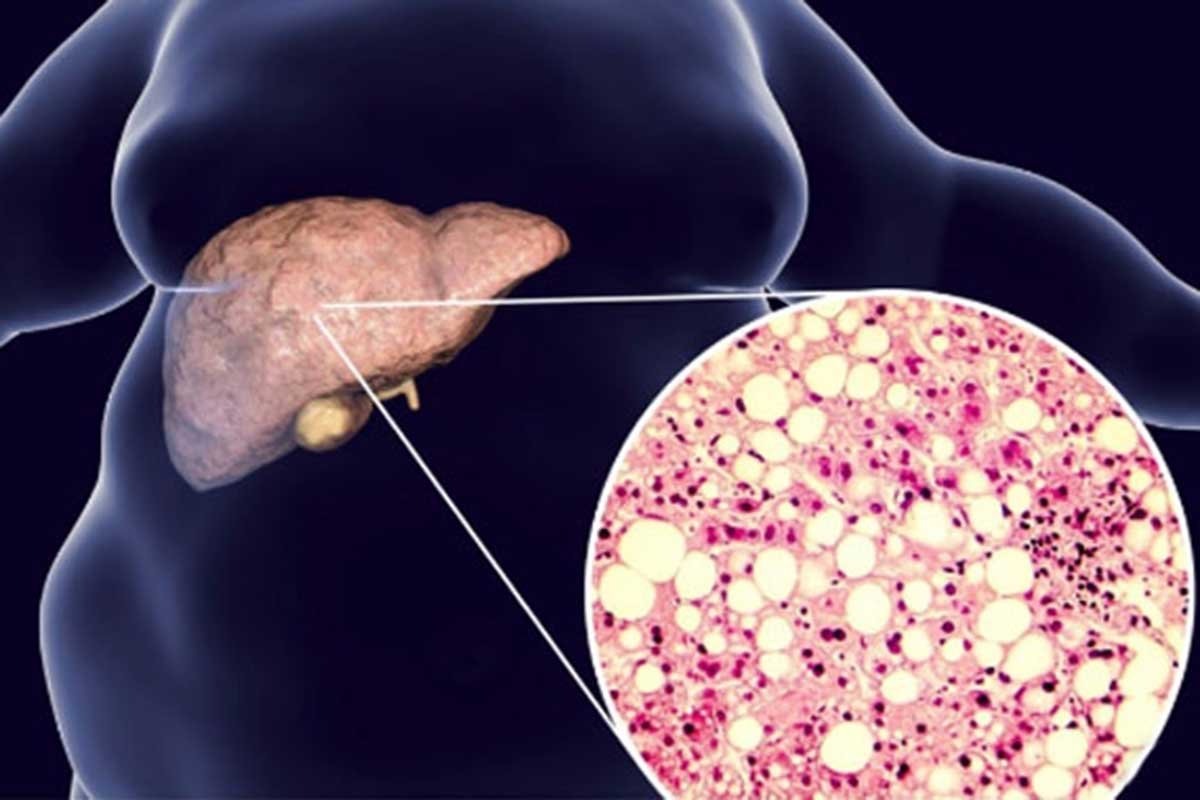

Jetra može dugo biti oštećena bez jasnih simptoma, jer nema nervne završetke za bol. Zbog toga masna jetra često prolazi neprimijećeno, a prvi znaci su blagi i nespecifični. Zdrava jetra sadrži manje od pet posto masti, a kada taj procenat pređe pet do deset posto, govori se o steatozi. Iako je višak kilograma jedan od glavnih faktora rizika, bolest se može razviti i kod mršavih osoba, posebno ako postoji inzulinska rezistencija, povišeni trigliceridi i holesterol, genetska predispozicija ili nezdrav način života.

Visok unos prostih šećera, naročito fruktoze iz gaziranih pića i industrijskih proizvoda, nedovoljno kretanja, hronični stres i manjak sna dodatno opterećuju jetru, bez obzira na tjelesnu težinu. Ako se stanje ne otkrije i ne liječi na vrijeme, kod dijela pacijenata može napredovati u upalu jetre, zatim u fibrozu, cirozu, pa čak i rak jetre. Osim toga, masna jetra je povezana i s povećanim rizikom od srčanih bolesti i dijabetesa tipa 2.